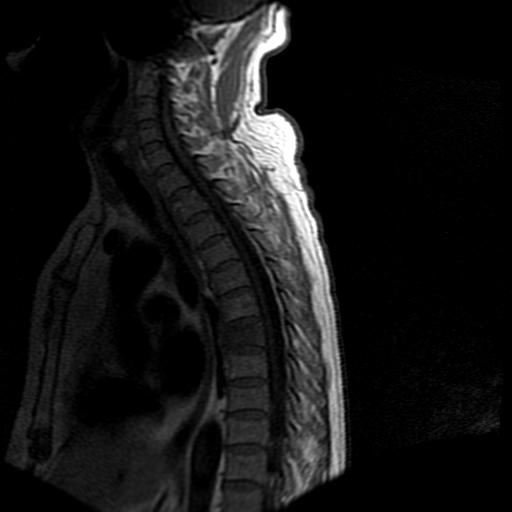

标题: MRI0985:胸椎.68岁男性,胸部疼痛,

68岁男性,胸部疼痛,不适。

t7椎体前1/3信号略减低,椎体上下面凹陷,相应脊髓几周边软组织信号未见改变。考虑:椎体退变。

胸7椎体楔状变形及信号异常,附件未见明显异常信号.椎间隙正常.未见软组织块影.考虑骨质疏松所致压缩性骨折可能大.

胸7椎体楔状变形及信号异常[t1t2 均为低信号],附件未见明显异常信号.椎间隙正常.未见软组织块影.考虑陈旧性压缩性骨折伴退变。

首先需除外单发成骨性转移瘤可能。

转移瘤也不能排除